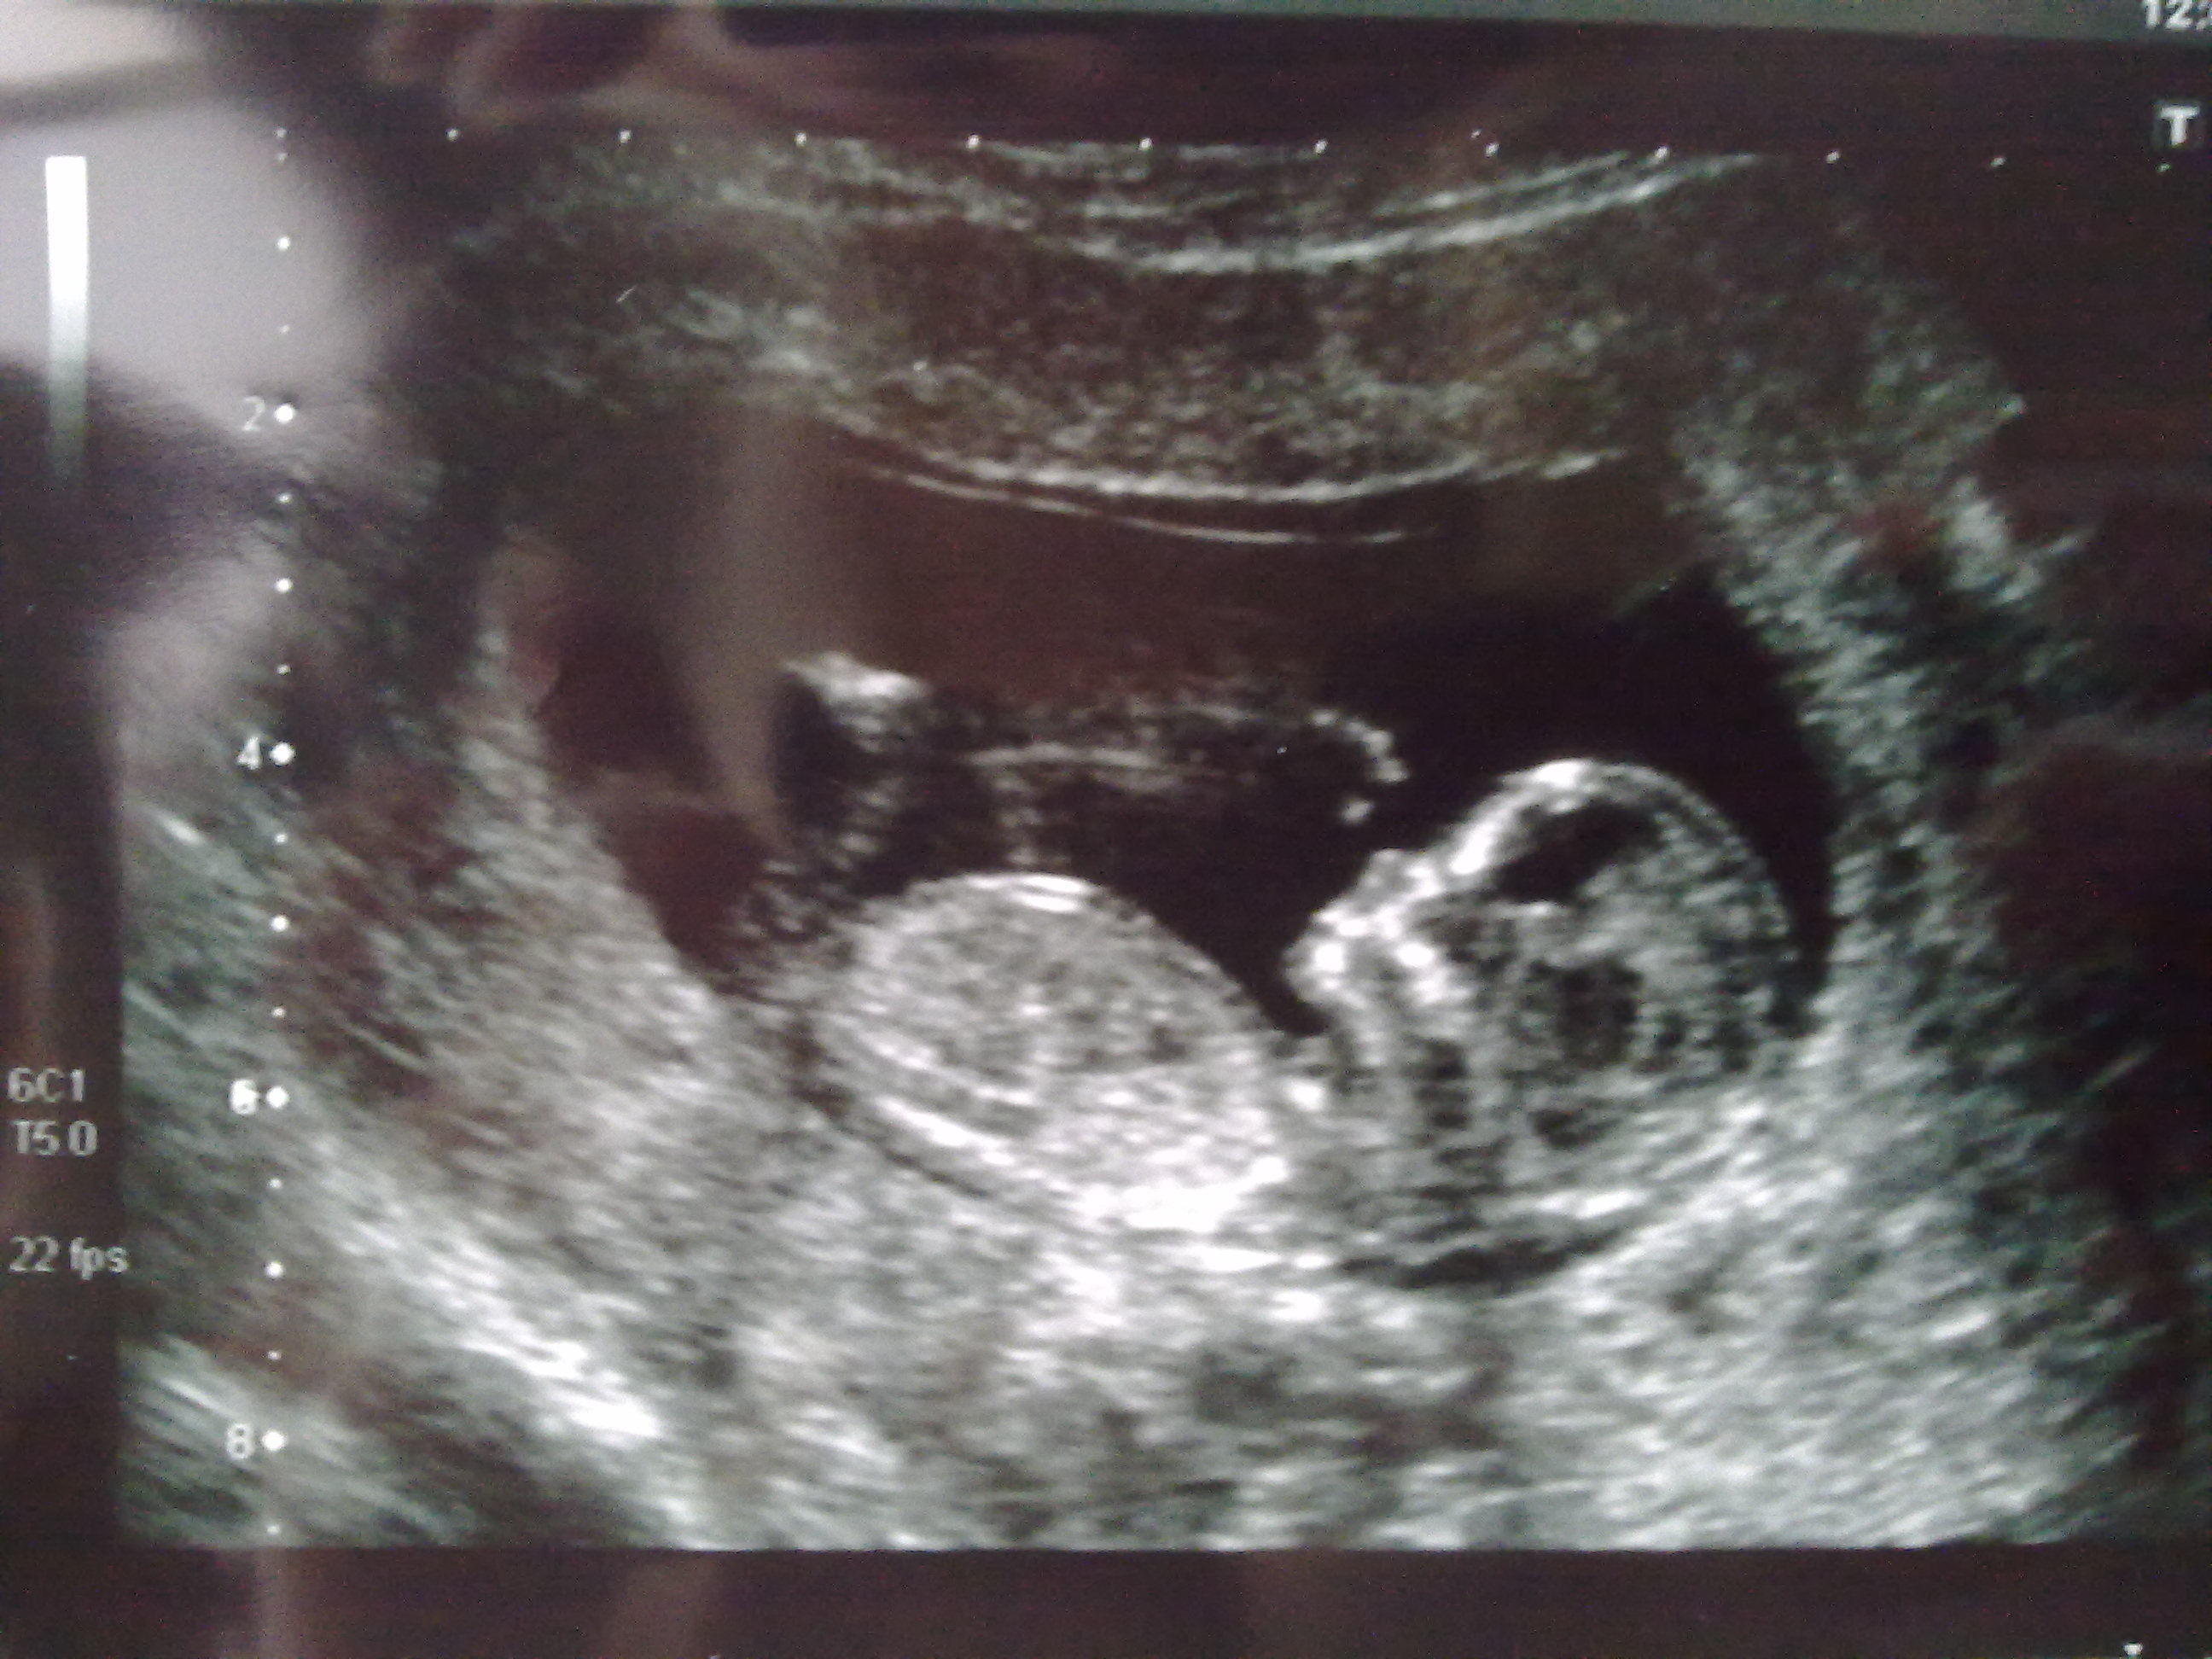

Prayn, this is the other shot I have x

Attachment 1324

looks girlie to met too, GL!

I think it looks really girlie, good luck!!

girly hun FX for pink x x

It looks like a girl!!

Thanks all. Boy confirmed at 20 week scan today x